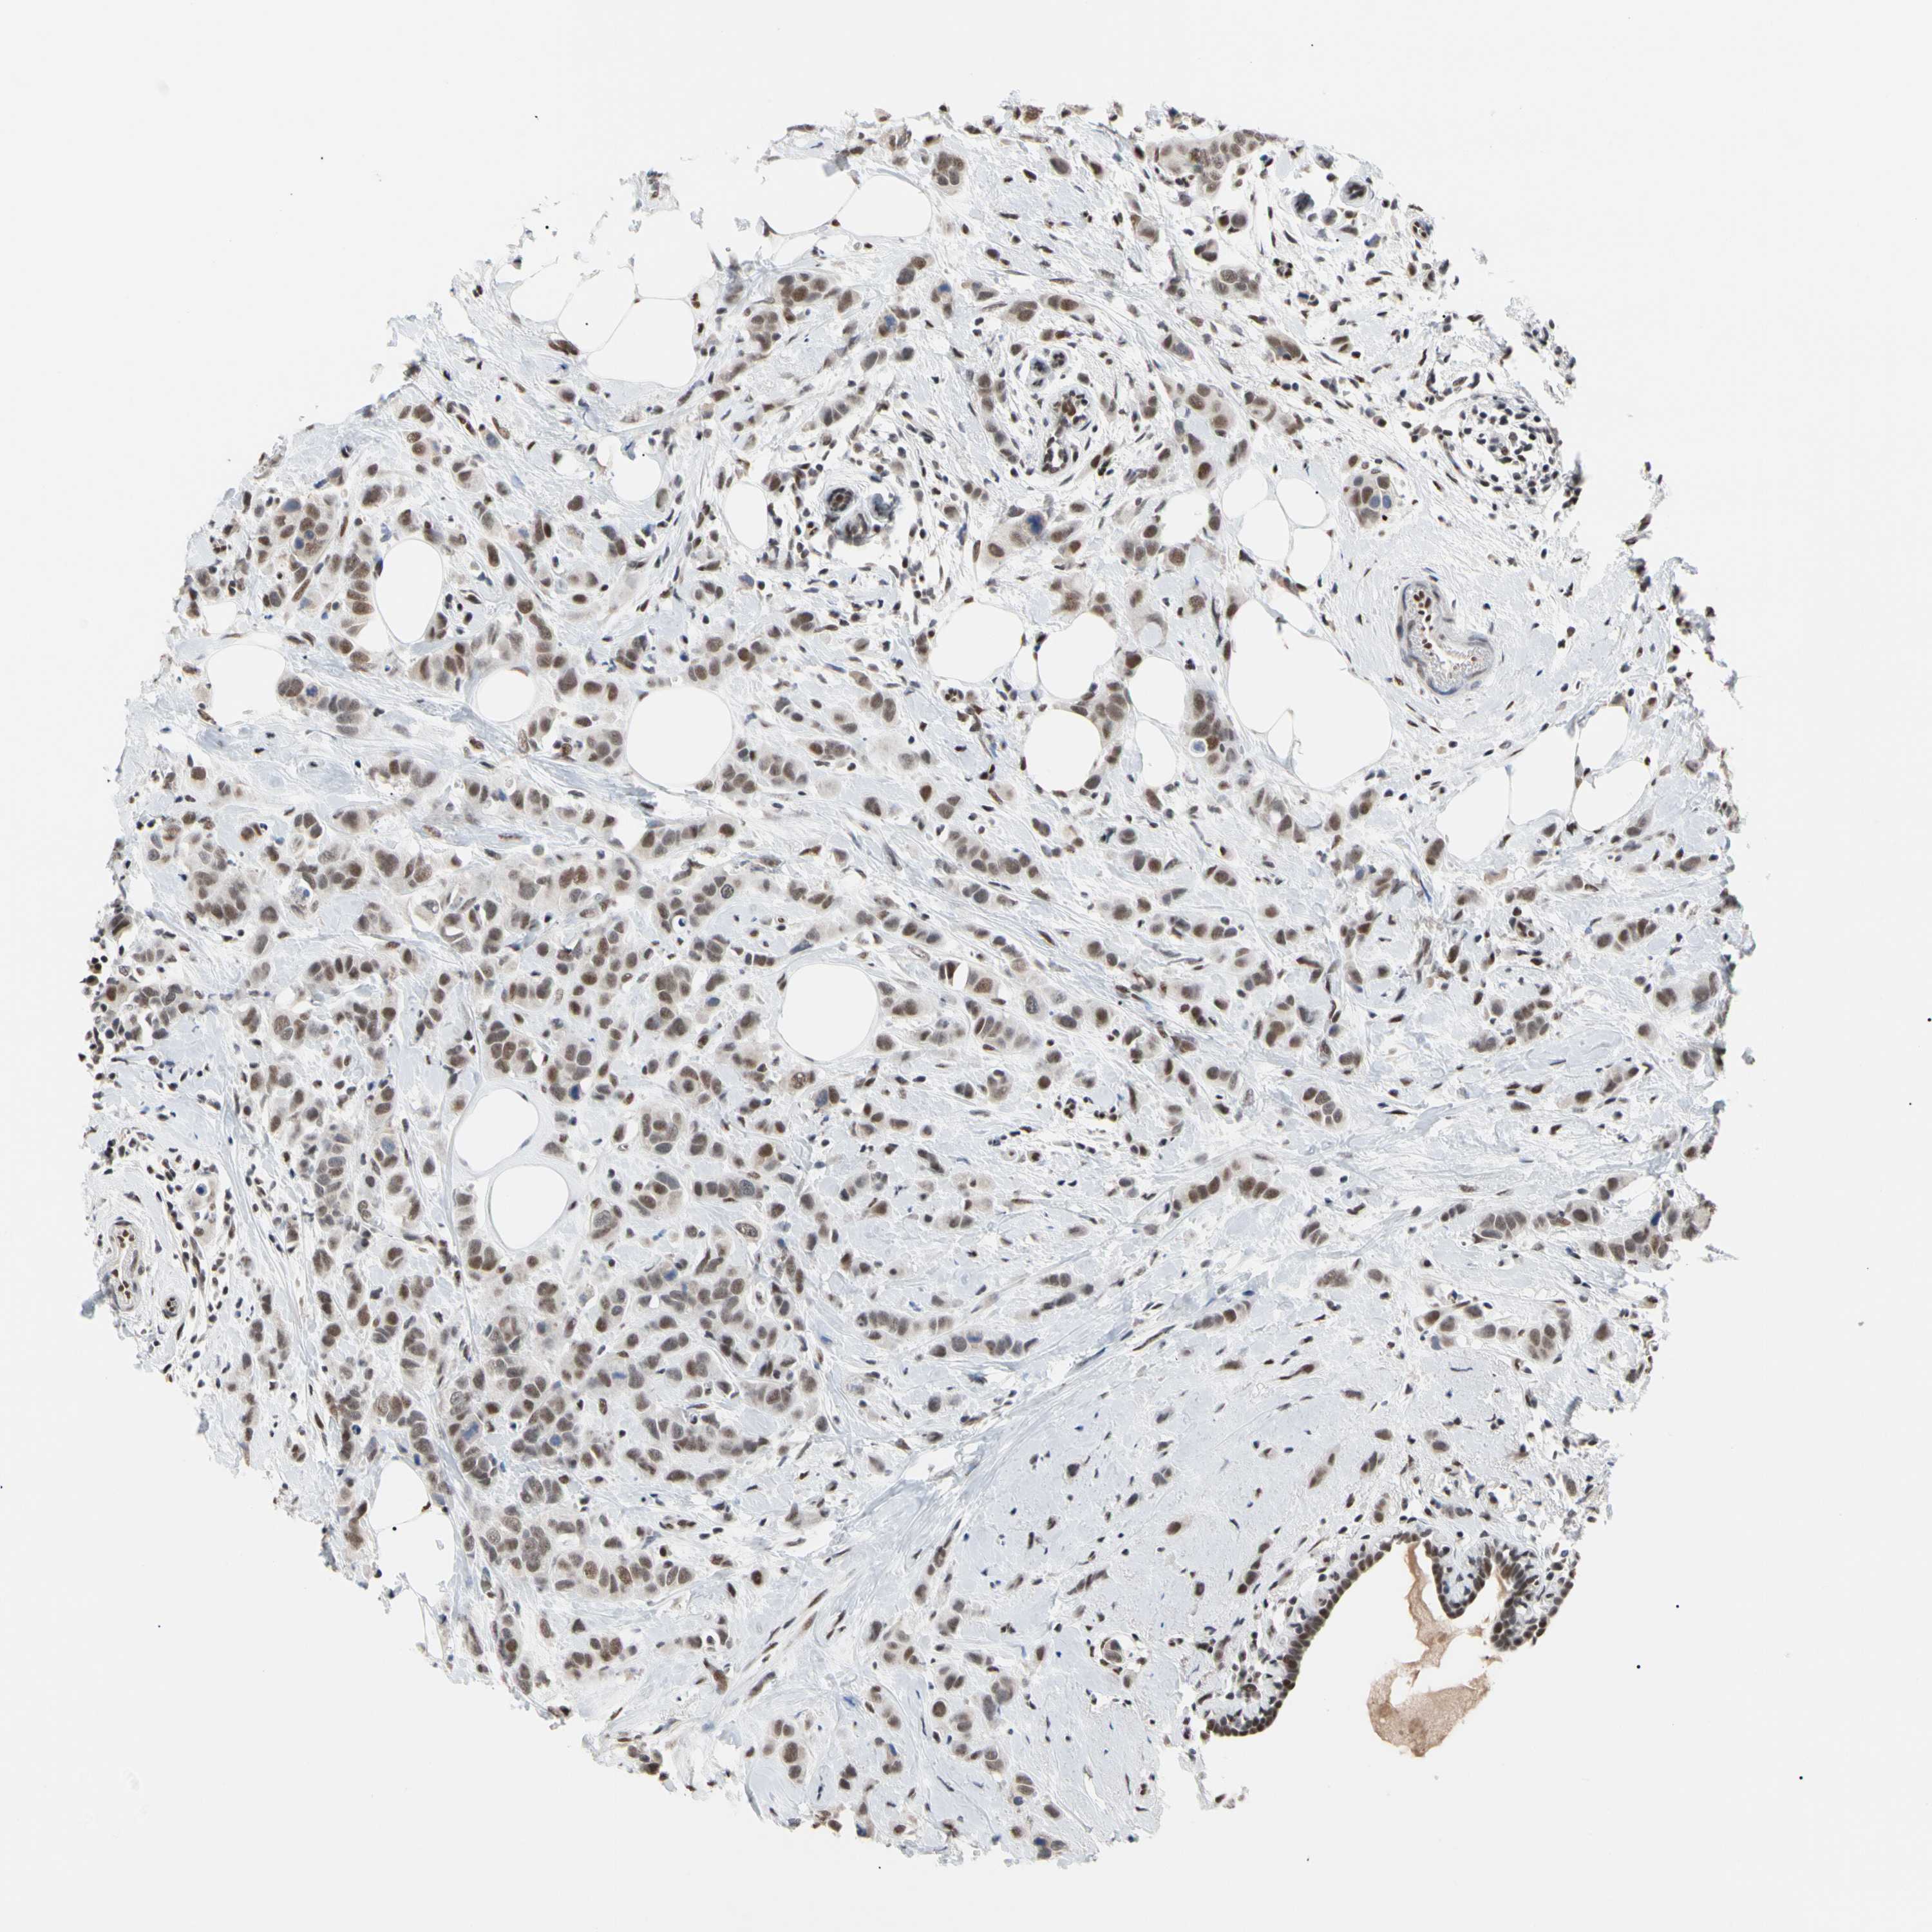

BRCA TCGA BRCA VALIDATION PROTEIN EXPRESSION

ANTIBODIES

AND

VALIDATION